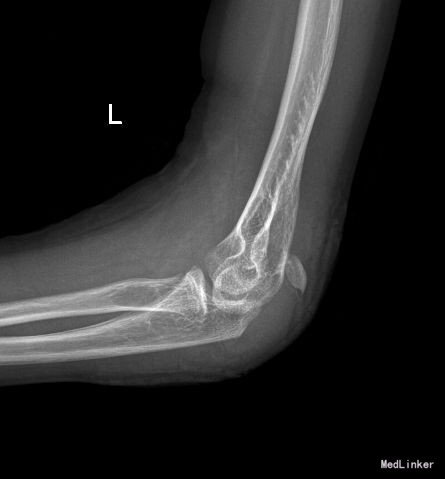

主 诉: 摔倒致左肘部疼痛伴活动受限7小时余。 现病史:约7小时前患者骑自行车时不慎摔倒,左上肢着地,当即出现左肘部疼痛伴活动受限,随即至当地医院行X线片检查示:左侧尺骨鹰嘴骨折。当时给予膏药外用及左上肢绷带悬吊,患者为求进一步诊治遂来我院就诊,门诊以“左侧尺骨鹰嘴骨折”为诊断收入我科,发病以来,神志清楚,精神尚可,无恶寒发热,饮食、大小便正常,睡眠可,体重无明显变化。

专科检查 步入病房。左上肢绷带悬吊,左肘部膏药覆盖。去除膏药后可见左肘外侧一长约4cm手术疤痕,肘关节肿胀明显,未见明显皮下淤血,皮肤张力稍高,肘关节后方局部压痛明显,左肘活动明显受限,左肘后方可触及一活动性骨块,左上肢皮肤感觉未见明显异常,左腕及手指活动可,末梢血运良好。

诊断:左侧尺骨鹰嘴骨骺骨折 治疗:臂丛麻醉下行“左尺骨鹰嘴骨骺骨折切复内固定术”